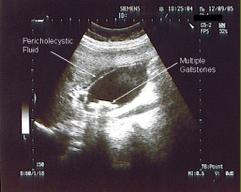

In an US, what are the dark areas and what are the white areas?

Echogenic (solid / white) masses with “shadowing” behind (mobile)

What finding is this describing on an US?

Gallstones

US Of what structure?

Gallbladder